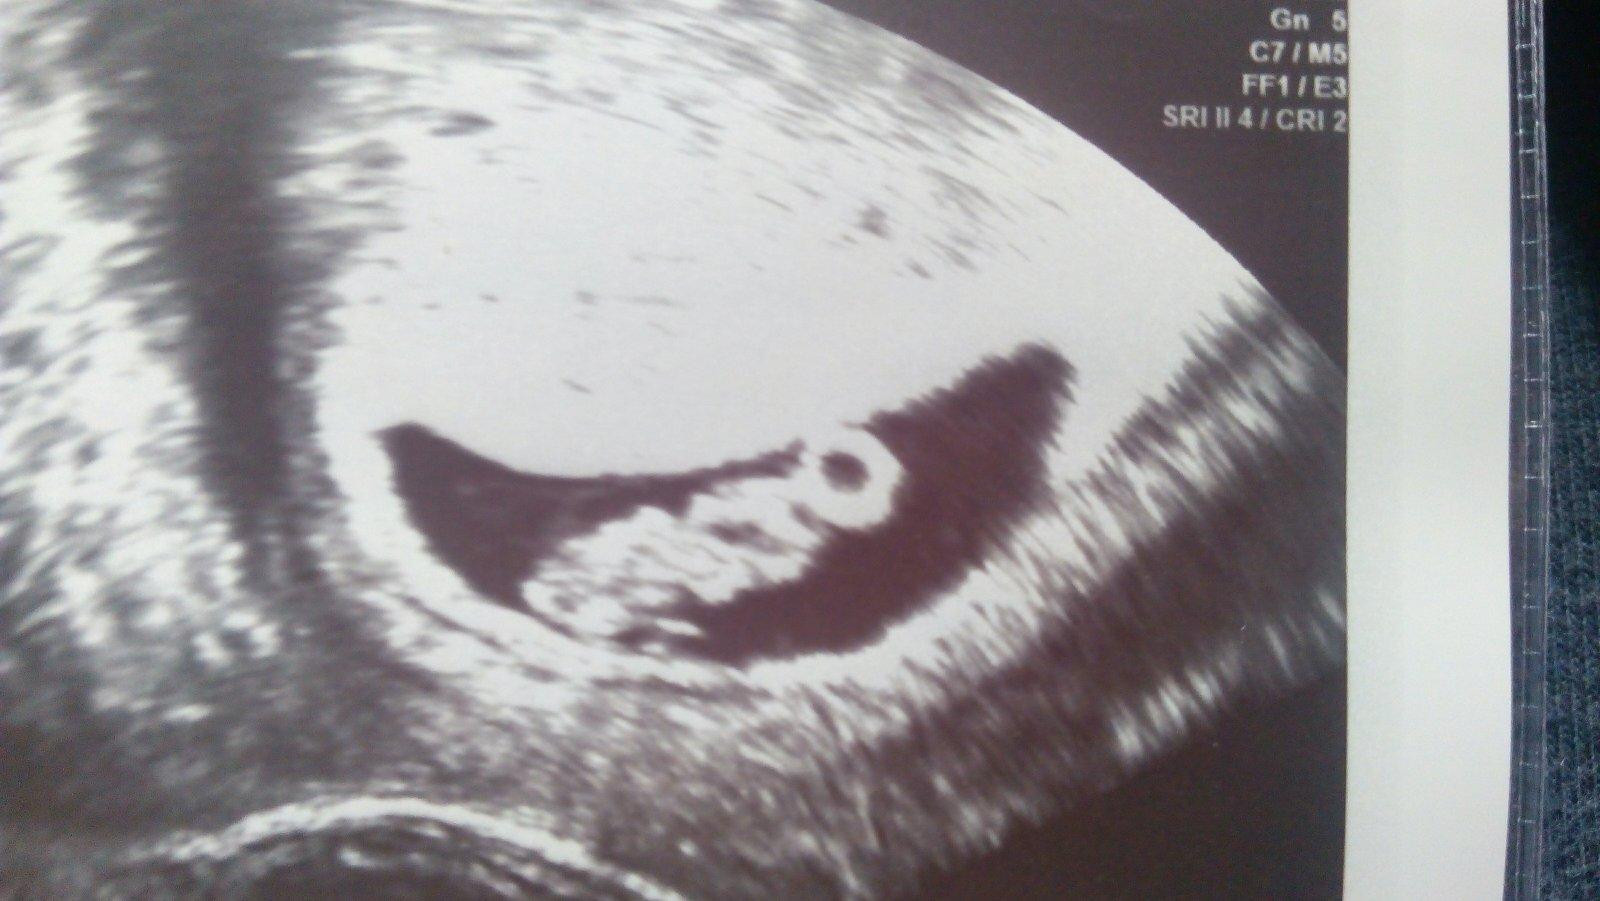

Ted jsem uz v pulce 7tt,pred 14ti dny jsem mela hcg pres 1600j, mam za sebou 3 zamlkle potraty,takze proste strach a to vymizeni priznaku,ktere je vzdycky provazelo. Ale tim,jak clovek nekrvaci,nema bolesti,tak neceka,ze mu doktorka se zkrousenym vyrazem oznami jw mi lito,nevidim akci. Na kontrolu jdu nastesti uz zitra,jestli je to zase v riti,tak chudak dokrorka,mam pocit,ze to nesla stejne blbe jako ja